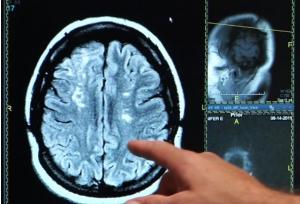

La fenêtre d'intervention est très courte, à la suite de l'AVC, rappellent les auteurs, « un laps de temps crucial pour recevoir les soins permettant de rétablir le flux sanguin et réduire ou inverser les dommages au cerveau ». Ce sondage montre que les patients plus jeunes, les adultes de moins de 45 ans, ont tendance à sous-estimer l'urgence des symptômes d'AVC au point de retarder leur prise en charge à l'hôpital. Le Dr David Liebeskind, professeur de neurologie, et auteur principal rappelle que plus le cerveau sera privé du flux sanguin ou envahit par l'hémorragie, plus dévastatrices seront les conséquences pour le patient.

L'AVC ischémique peut se produire à tout âge : La plupart des jeunes patients, environ 85% souffrent d'AVC ischémique, conséquence du manque d'apport d'oxygène dans une partie du cerveau lié à un blocage des artères. L'AVC ischémique est souvent associée à l'hypertension artérielle, au diabète, au tabagisme et à l'obésité. Mais les mesures de mode de vie, comme une alimentation équilibrée, la pratique régulière de l'exercice, l'absence de tabagisme et d'excès d'alcool, contribuent à réduire le risque d'AVC.